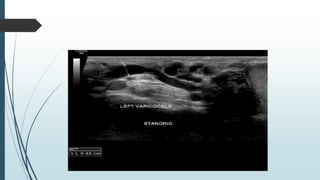

Varicocele

Dilatation of the network of veins draining the

testicle is described as a varicocele.

They are extremely common.

Usually asymptomatic.

Most frequent between 15 and 25 years of

age.

Almost always left sided

When symptomatic, present with scrotal

aching and/or soft mass.

On ultrasound varicoceles are seen as a leash

of predominantly echo-free serpiginous

structures measuring more then 2mm

maximum diameter.

Visible flow may be seen within large

varicoceles on conventional ultrasound.

 Evaluation

 Baseline greyscale study in supine position and

measure the diameters of veins, as well as the total

diameter of the plexus.

 Next do colour Doppler interrogation and see reflux

during valsalva manoeuvre.

 Repeat in standing position.